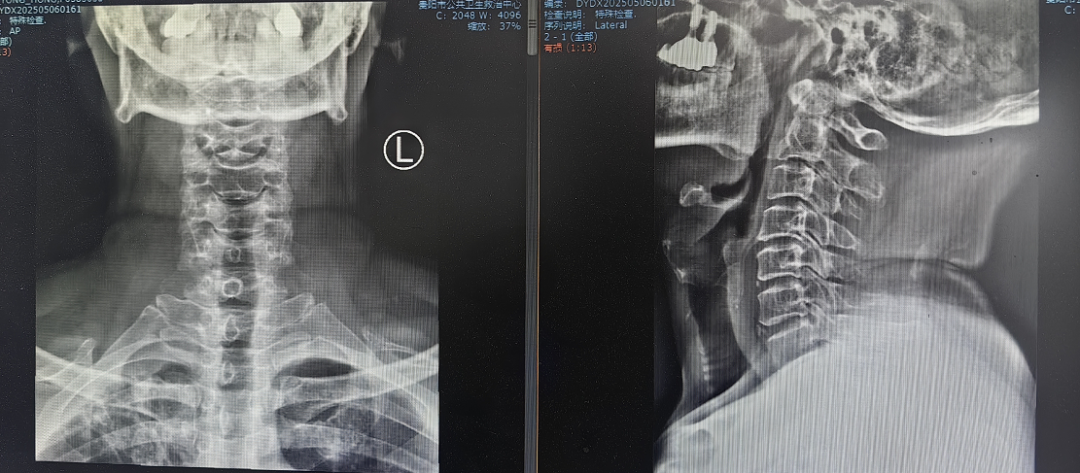

患者因"頭痛、雙上肢麻木伴下肢乏力1月"入院,此前長期保守治療效果不佳,癥狀持續(xù)加重并出現(xiàn)行走不穩(wěn)。經(jīng)多學科聯(lián)合會診,團隊決定采用國際先進的零切跡cage融合術。手術歷時2小時,出血量僅10ml,術后患者即刻感到頸部及肢體癥狀顯著緩解,術后三天即可下床活動,微創(chuàng)切口(3—4厘米)及快速康復效果獲家屬高度贊譽。

相較于傳統(tǒng)鋼板融合術,零切跡cage融合術實現(xiàn)了技術升級。

1.采用小型化、低切跡的融合器(cage),切口僅3—4厘米,術中對軟組織剝離少,有效降低血管、神經(jīng)損傷風險;

2.其零切跡設計貼合頸椎生理曲度,減少對食管刺激,避免術后吞咽不適;

3.cage融合可促進骨組織自然生長,穩(wěn)定性佳,能更好地維持頸椎活動度,加速患者術后康復進程,縮短住院時間。